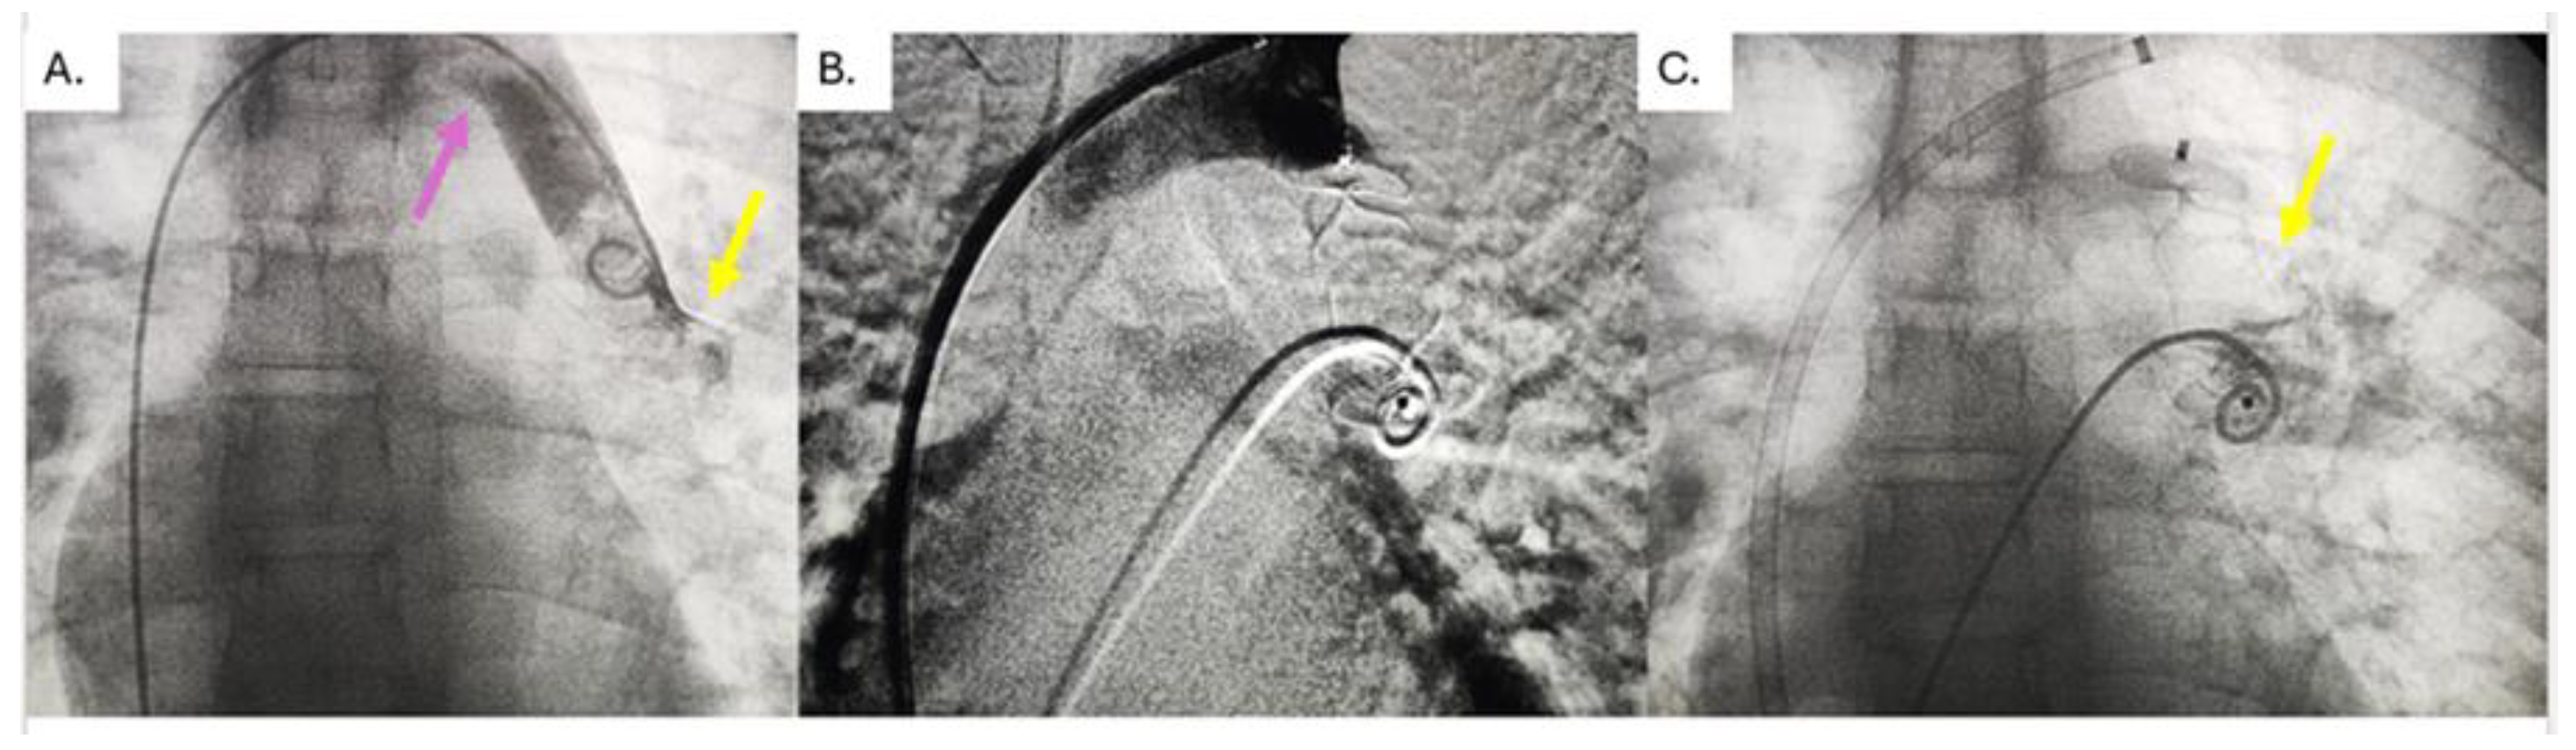

Percutaneous Embolization of No Ligated Vertical Veins After Total Anomalous Pulmonary Vein Return Operation and Risk Factors for Its Persistence